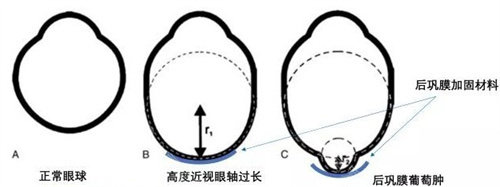

术中:使用龙晶PR人工晶体(国产初款睫状沟固定型晶体)增强角膜稳定性